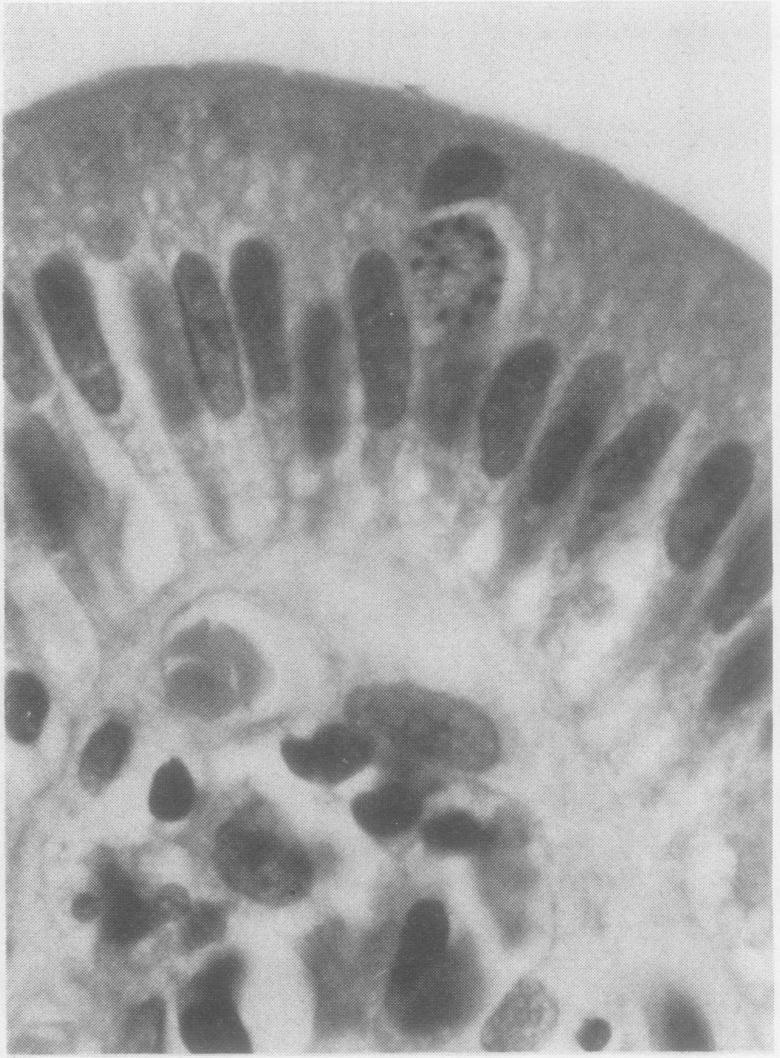

Opportunistic protozoan infections in human immunodeficiency virus disease: review highlighting diagnostic and therapeutic aspects.

摘要